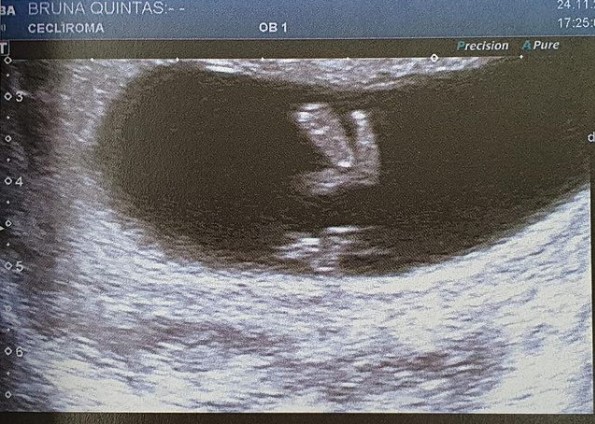

Bald nach der Ankündigung des Werfens kündigten Bruna und Guilherme die Schwangerschaft der Schauspielerin im Dezember an und veröffentlichten das Bild eines Ultraschalls. In beiden Instagram-Profilen haben sie das Foto mit der Beschriftung gepostet: "FEEPS fünfte Moura".